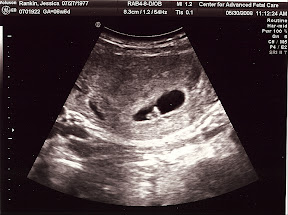

You can only imagine my surprise when I saw not a dead bug but a real live baby! Here's a picture of our first look at what will, on my 3rd birthday, be my baby brother or sister. Yes, mom is due on January 19th, 2009. A day that is filled with so much significance and so many blessings for our family. Not only is it the day that I was born in 2006, but my sister Talitha Grace was taken to see Jesus that day in 2007, and now it's the possible day that our family will be given another wonderful blessing with the birth of another child.

This is a long awaited and greatly prayed for moment for all of us. We have been very excited and God has shown us so much mercy as the pregnancy has progressed. We saw the heartbeat at that first ultrasound which gave us confidence in the blessing the Lord has bestowed upon us. At our first Dr.'s appointment, 8 weeks, this baby had the earliest heartbeat our Dr. has ever heard externally with a doppler, another glorious mercy given to us. And then yet again at the 11 week mark the ultrasound revealed that we have been blessed with a healthy baby.